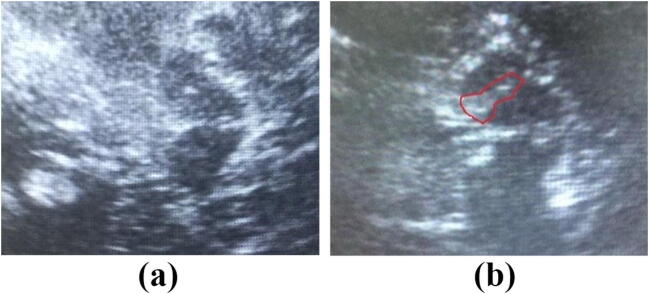

Through the preauricular acoustic bone window, a qualified operator, who was blind to the clinical information of the subjects, examined the echogenicity of the SN using a 1.82 MHz sonographic device (ACUSON Anteres, SIEMENS) with a depth of 15–18 cm and a dynamic range of 26 dB. The SN was scanned through both temporal bone windows in the axial plane. After identifying the butterfly-shaped hypoechogenic midbrain surrounded by the hyperechogenic of basal cistern, the clearest image of the hyperechogenic signal in the SN region was stored (Fig. 1). The areas of SN hyperechogenicity in the midbrain were measured manually by the same operator.

Fig. 1.

Sonographic images of the mesencephalic brainstem in a healthy control (a) and a patient with Parkinson’s disease (b). The butterfly-shaped mesencephalic brainstem was surrounded by the hyperechogenic basal cisterns. The patient with Parkinson’s disease exhibited hyperechogenic signals encircled by lines at both sides of SN, which were not seen in the control